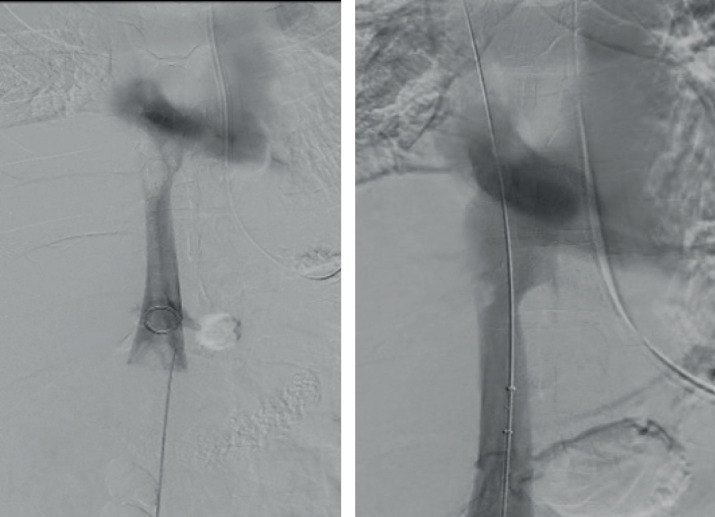

Case presentation: The patient was brought to emergency department and was successfully managed by angio-jet thrombolysis. He developed a transient contrast nephropathy that was recovered after continuous renal replacement therapy. Several management options have been proposed in the literature, including conservative, endovascular and operative management.

Conclusion: Angio-jet is a recent promising technique for managing of venous thrombosis. However, its use in cases of IVC-Th is not extensively discussed in the literature.